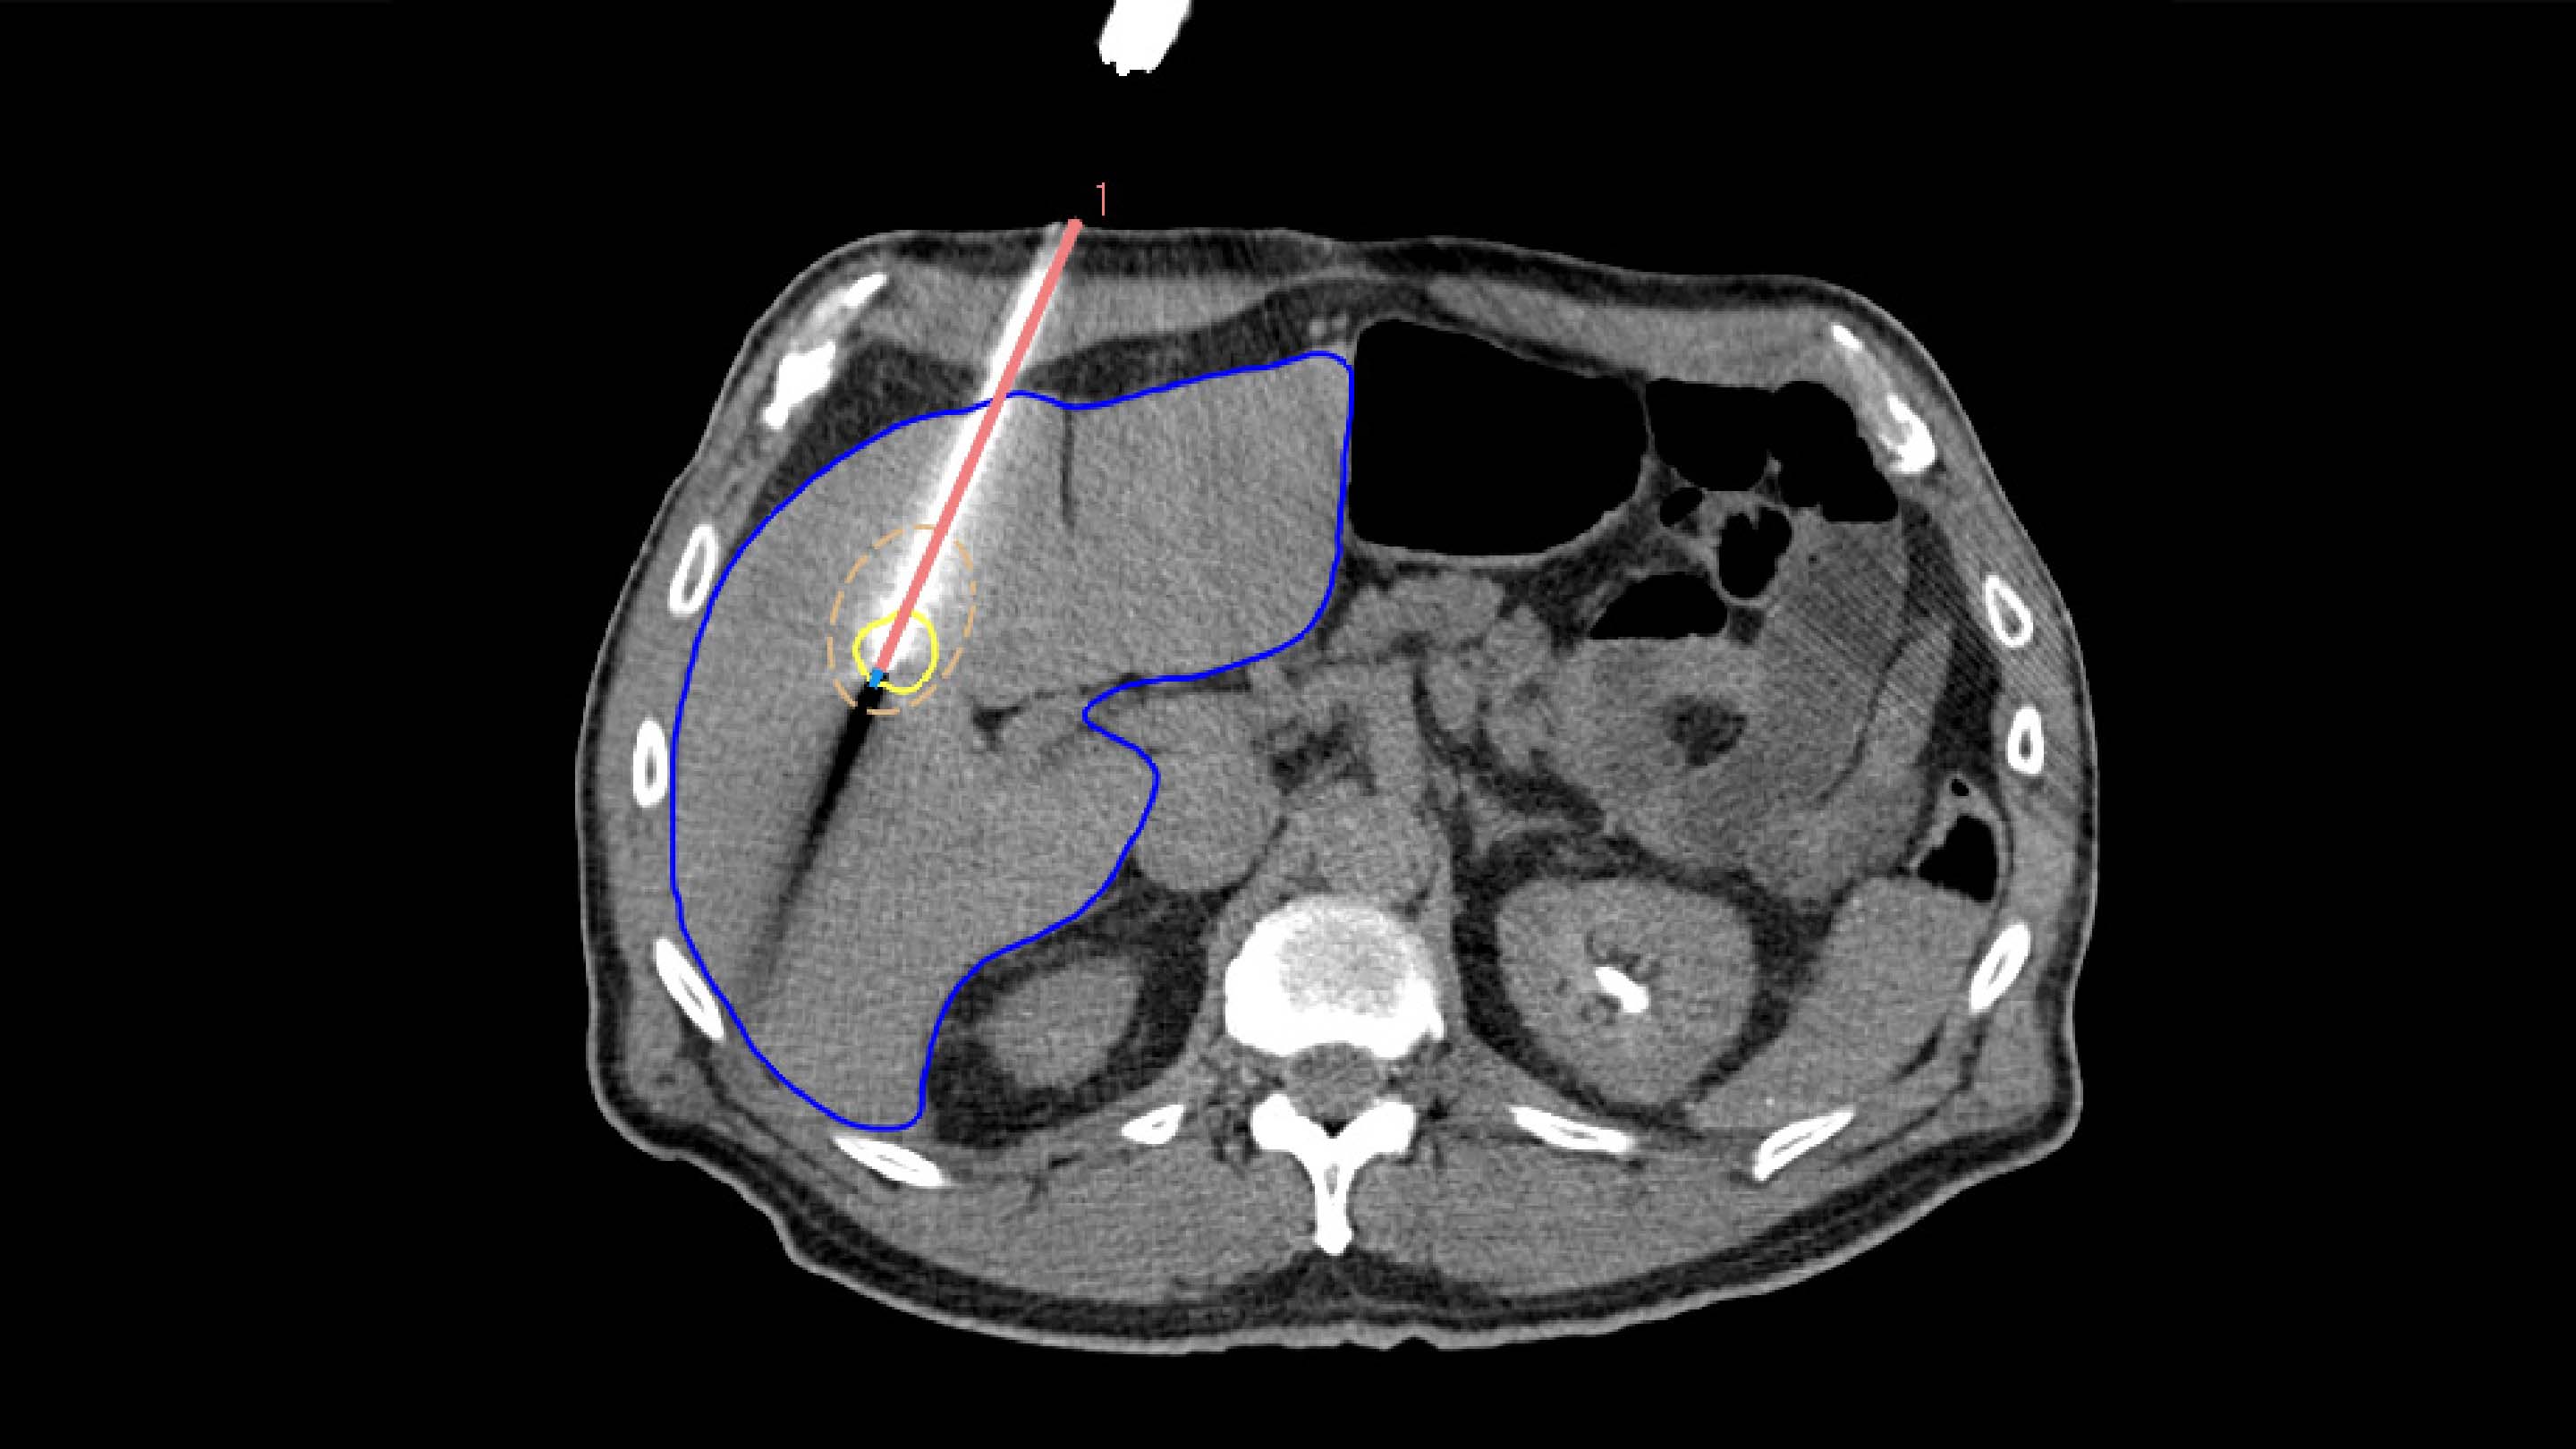

To ensure accurate applicator placement before treatment, the segmented tumors from the planning phase are mapped using deformable registration, allowing for a visualization of the anticipated tumor position. Additionally, the ablation zone can be estimated based on the applicator parameters, such as its current position, selected power, and ablation duration.